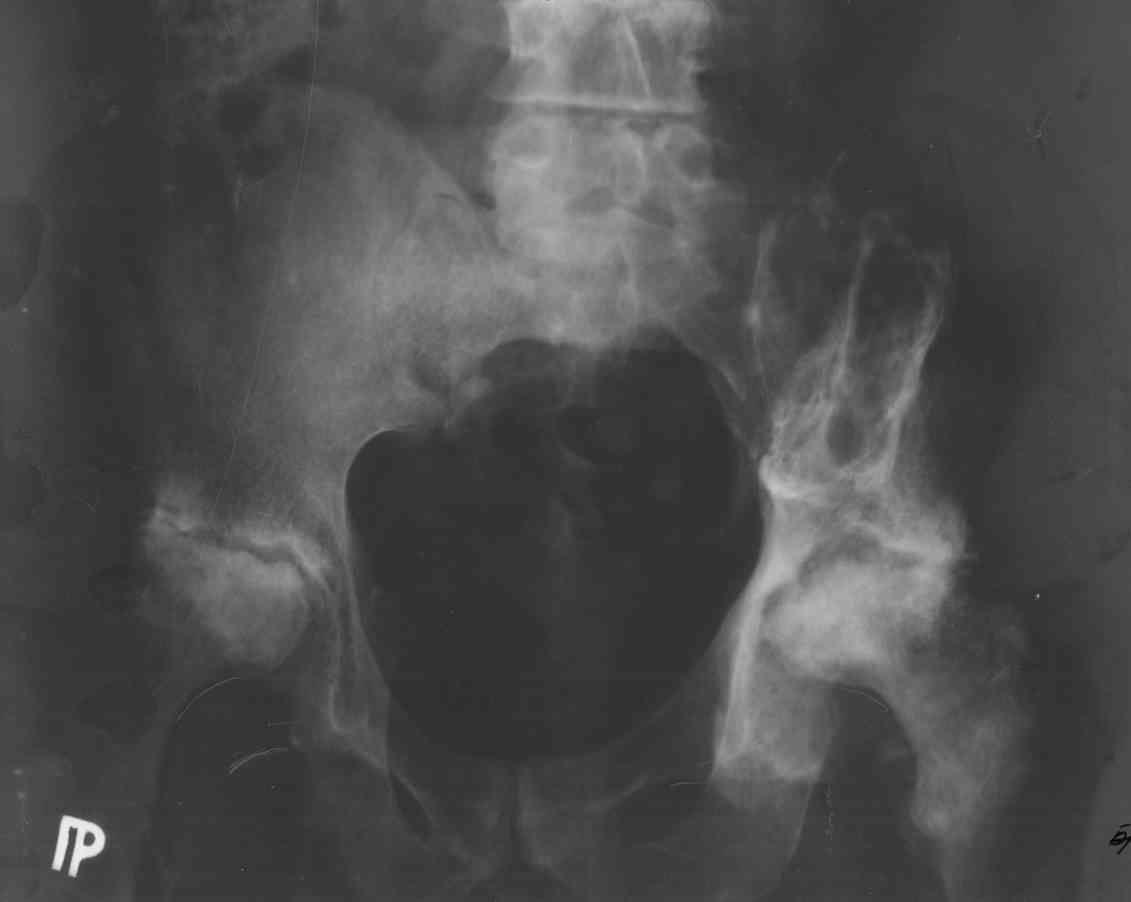

Re: Эндопротез и миелома

послал Каминский Андрей 15 Август 2007, 16:53

Возможно это очаги болезни. Прилагаю снимок.